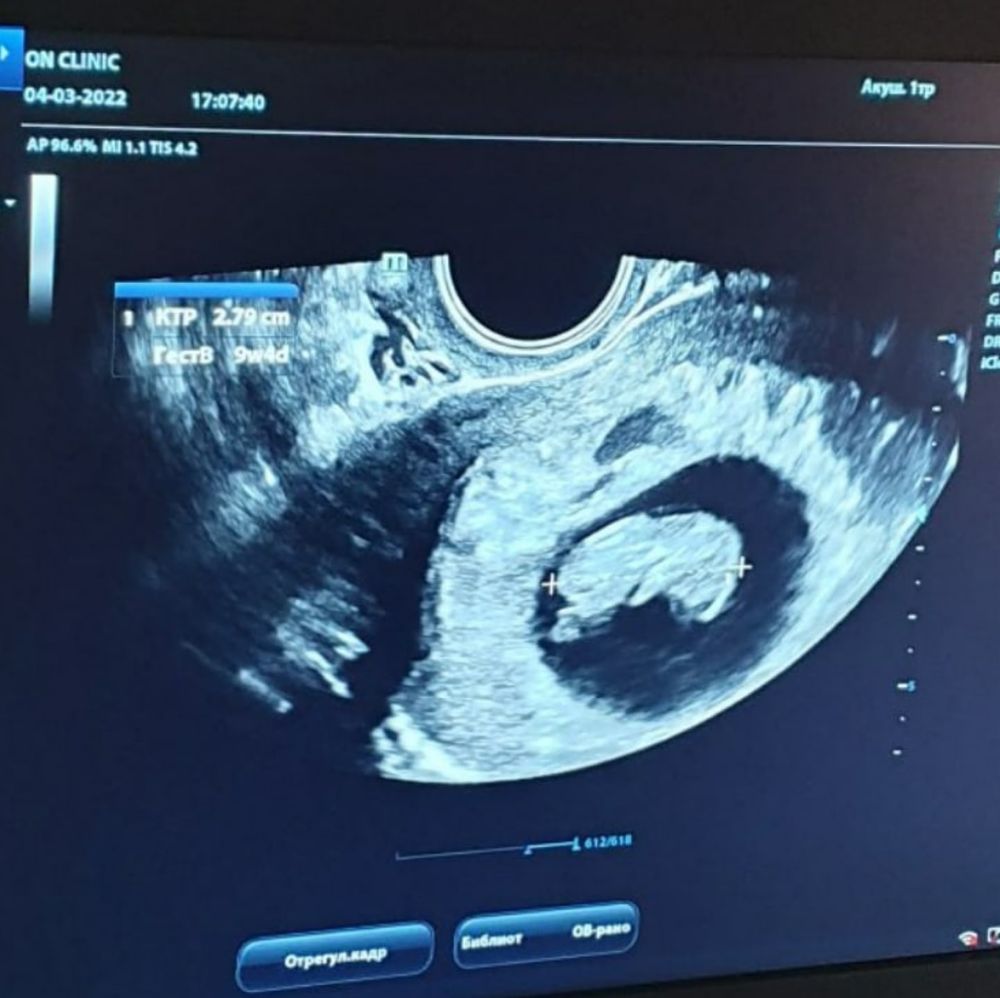

9.5 недель

Сегодня была на узи. Впервые померили сердцебиение 163 удара, чёткое.

Ктр уже 29мм! Такой большой малыш 🥰 по ктр срок 9.6 вообще)

Уже появился хорион, хороший, прикрепление по передней стенке.

Очень жду теперь скрининг. Малыш сегодня шевелил ручками и ножками. Животик закрыт, все хорошо